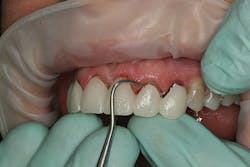

At the beginning of the impression appointment, the provisionals were approved for fit and esthetics with a particular focus on emergence profile of the implant provisionals. Profound anesthesia was achieved and the bisacrylic provisionals were removed. The preparations were cleaned with chlorhexidine (Consepsis, Ultradent) and the abutments were once again removed (figure 10). The open-tray impression copings were then tried in, their seat confirmed radiographically, and then modified into custom impression copings with flowable composite (figures 11-14). Once appropriate tissue support was confirmed, the open-tray master impression was made with a heavy and light body wash technique using vinyl polysiloxane impression material (Honigum, DMG America) (figure 15). Following the master records, the provisional abutments and bisacrylic provisionals were replaced until the seat appointment.

Figure 11

Figure 12

Figure 13

Figure 14